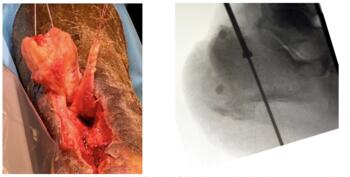

Achilles tendon ruptures, commonly seen in the active population, have no associated consensus on whether such tears require surgical treatment. The incidence of Achilles tendon ruptures is 18:100,000 per year and occur more commonly in men aged 30 to 40 years.1,2 Studies show that 60 percent of Achilles tendon ruptures are sports-related.3 Fluoroquinolones have been associated with tendon ruptures in patients who have renal dysfunction.4 Histopathologic studies show that ruptured Achilles tendons have tissue and cell necrosis, calcification, irregular and degenerated collagen fibers around the rupture site.5 Surgical options for the treatment of Achilles tendon ruptures include end-to-end Achilles tendon repair and percutaneous or mini-open Achilles tendon repair. Furthermore, augmentation to the repair may also include V-Y advancement (Figure 1) or FHL tendon transfer (Figure 2). There is a growing body of research in support of functional rehabilitation for non-surgical treatment of acute Achilles tendon ruptures.6,7 Recommendations on how to treat acute Achilles tendon ruptures has become controversial and requires an open dialogue with the patient and family to make the best decision for the situation.